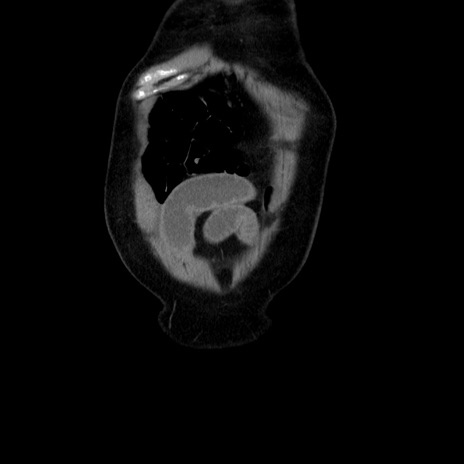

横断像